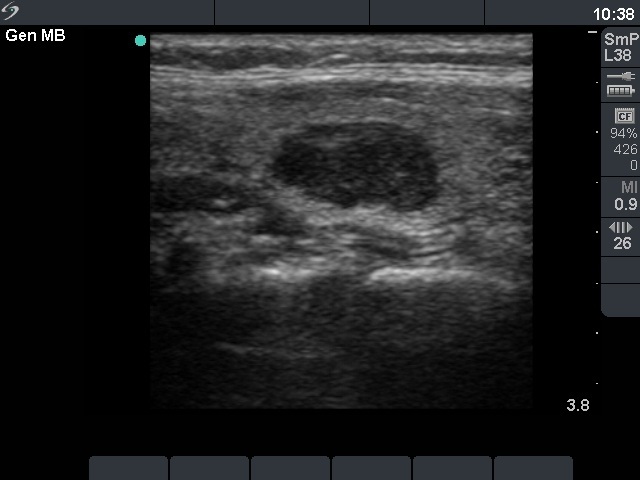

Benign nodular hyperplasia - Case 23. (ultrasonographic picture 5)

Right lobe, the previous nodule on longitudinal scan.